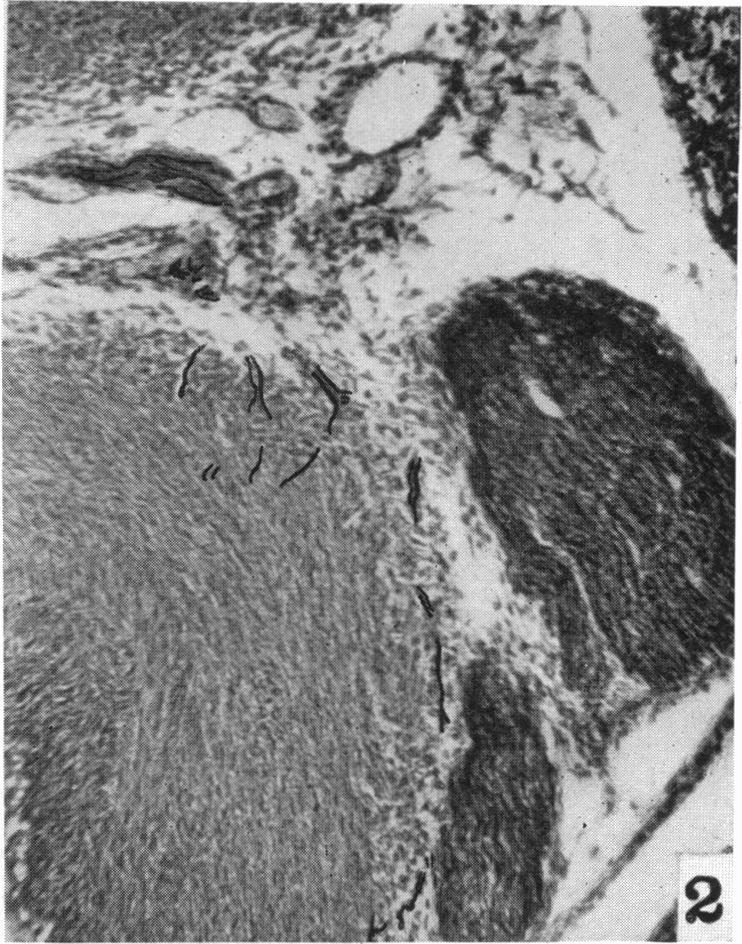

The nerve supply of the mammalian ductus arteriosus.

摘要